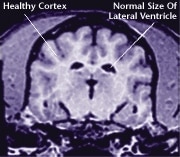

Just like the rest of the body, the brain is affected by the aging process. Damage to the brain’s cells can lead to changes in your dog’s behavior and alertness.

It's important to remember that aging is a natural part of your dog's life. Half of all dogs 8 years and older will show some signs of brain aging, and as your dog ages, he may begin to act differently. Thanks to advances in medicine and pet nutrition, the right dog food and veterinary advice can help limit the effects of brain aging and maintain your dog’s activity level.

Aging takes a toll on a dog's entire body, including his brain. In recent years, scientists have made great strides in understanding the aging process. Today, many experts agree that aging is primarily caused by unstable oxygen molecules called free radicals. As the brain ages, free radicals cause damage to the cells. Although some free radicals may be caused by the effects of environmental conditions, the majority are produced by the body’s own metabolism.

The aging process attacks all body systems and organs in a dog, including the brain. The result is a loss of brain function, and often, the appearance of behavioral changes that were not present in a dog’s younger years.

![]() Healthy Older Brain | ![]() Older Brain with Damage |

| MRI scans show loss of brain tissue in affected dogs. Note: MRI scans are not harmful to dogs. | |